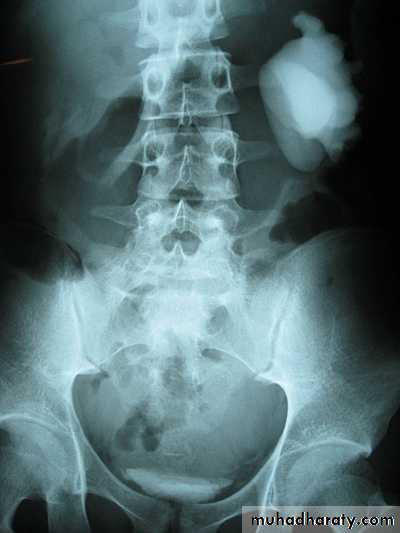

*Right kideny is ectopic(presacrally located)&bilateral hydronephrosis.